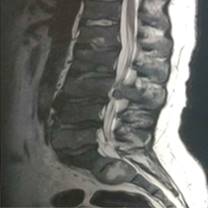

La resonancia magnética nuclear vertebral demostró una lesión vertebral tumoral en T5 extracompartimental con afectación medular y paravertebral, con extensión hacia los elementos posteriores vertebrales.

En la región sacra se evidenció una lesión tumoral hiperintensa de bordes regulares, redonda, la cual se alojaba en el cuerpo vertebral de S2 (Figura 6), así como la presencia de múltiples cuerpos vertebrales torácicos y lumbares afectados por lesiones de características similares. Finalmente, tres días después de su reingreso, el paciente fallece a causa de un tromboembolismo pulmonar fulminante.